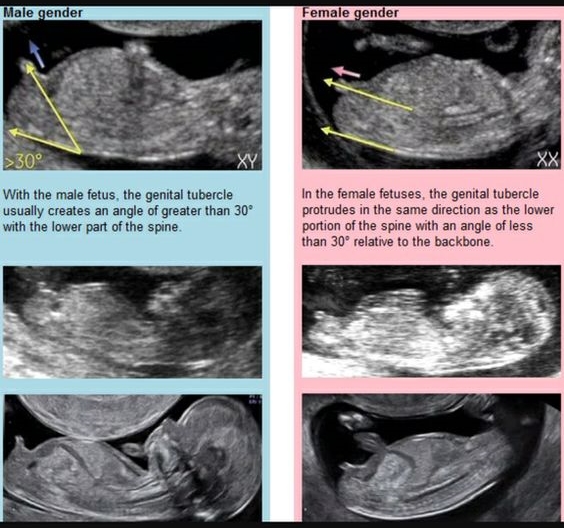

Macam mana nak bezakan lelaki dan perempuan?

Boleh refer gambar ni, tapi tu lah, sampai sekarang kalau tengok dekat gambar scan pun tak faham. Doktor atau sono je lah yang faham.